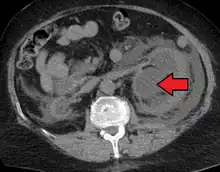

Hydronephrosis due to a kidney stone at the ureteral vesicular junction seen on CT scan

Prenatal diagnosis is possible,[7] and in fact, most cases in pediatric patients are incidentally detected by routine screening ultrasounds obtained during pregnancy.[8] However, approximately half of all prenatally identified hydronephrosis is transient, and resolves by the time the infant is born, and in another 15%, the hydronephrosis persists but is not associated with urinary tract obstruction (so-called non-refluxing, non-obstructive hydronephrosis). For these children, regression of the hydronephrosis occurs spontaneously, usually by age 3. However, in the remaining 35% of cases of prenatal hydronephrosis, a pathological condition can be identified postnatally.[9]

The choice of imaging depends on the clinical presentation (history, symptoms and examination findings). In the case of renal colic (one sided loin pain usually accompanied by a trace of blood in the urine) the initial investigation is usually a spiral or helical CT scan. This has the advantage of showing whether there is any obstruction of flow of urine causing hydronephrosis as well as demonstrating the function of the other kidney. Many stones are not visible on plain X-ray or IVU but 99% of stones are visible on CT and therefore CT is becoming a common choice of initial investigation. CT is not used, however, when there is a reason to avoid radiation exposure, e.g. in pregnancy.[11][12]